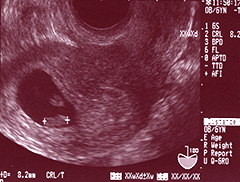

妊娠6週4日頃、CRL(頭殿長)8.2mm。

胎芽の上には卵黄嚢が。